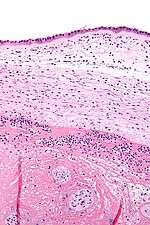

Micrograph showing chorioamnionitis. The clusters of blue dots are inflammatory cells (neutrophils, eosinophils and lymphocytes). H&E stain. | |

Chorioamnionitis can be diagnosed from a histologic examination of the fetal membranes.

Infiltration of the chorionic plate by neutrophils is diagnostic of (mild) chorioamnionitis. More severe chorioamnionitis involves subamniotic tissue and may have fetal membrane necrosis and/or abscess formation.

Severe chorioamnionitis may be accompanied by vasculitis of the umbilical blood vessels (due to the fetus' inflammatory cells) and, if very severe, funisitis (inflammation of the umbilical cord's connective tissue).